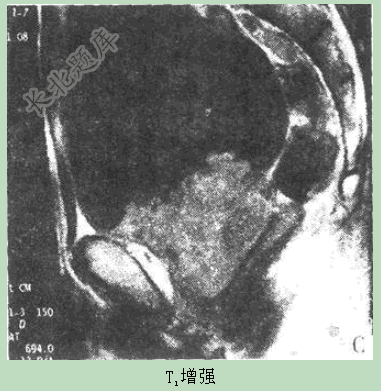

- 单项选择题患者男性,74岁,进行性排尿困难4月,MR图像如下,最有可能的诊断是( )。

D、前列腺癌